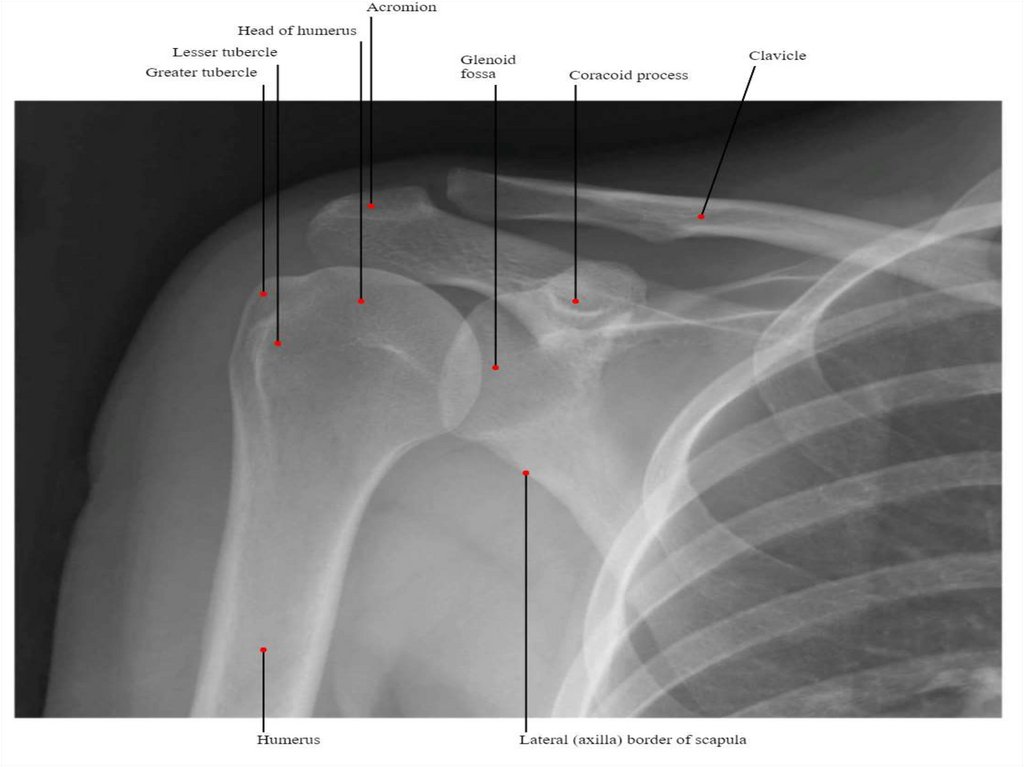

Плечова кістка – humerus

Вона складається з головки,

тіла і виростка.

Є складовою частиною плеча і

належить до типової

(трубчастої) довгої кістки, яка

має:

- проксимальний виросток,

епіфіз (проксимальний кінець)

- дистальний виросток, епіфіз

(дистальний кінець)

- тіло плечової кістки, діафіз.

18.

На проксимальному

епіфізі міститься головка

плечової кістки, на якій

міститься суглобова

поверхня для з’єднання з

лопаткою.

19.

Головку плечової кістки

відмежовує анатомічна шийка, під

якою на задньобічній поверхні

кістки міститься великий горбок, а

на передній поверхні – малий

горбок. Кожен із них переходить у

свій гребінь – гребінь великого

горбка; бічну губу і гребінь малого

горбка; присередню губу, між

якими знаходиться міжгорбкова

борозна.

На межі між проксимальним

наростком і тілом кістки

розташована хірургічна шийка

плечової кістки.

Тіло плечової кістки має передню

поверхню, задню поверхню,

присередній край і бічний край.

20.

Передня поверхня тіла

плечової кістки поділяється на

передньомедіальну поверхню, а

також передньолатеральну

поверхню.

На верхній третині задньої

поверхні тіла плечової кістки

міститься дельтоподібна

горбистість, дозаду і донизу від

якої проходить борозна

променевого нерва.

На дистальному наростку

міститься виросток плечової

кістки, а на ньому – блок

плечової кістки, що

розташований медіально; збоку

від блока – головка плечової

кістки.

21.

Над блоком плечової кістки

допереду міститься вінцева ямка, а

над головкою – променева ямка.

На задній поверхні навпроти цих

ямок розташована ліктьова ямка.

На краях дистального наростка

плечової кістки містяться

присередній надвиросток та

бічний надвиросток.

Між присереднім надвиростком і

блоком плечової кістки проходить

борозна ліктьового нерва.

На присередньому краї тіла

плечової кістки міститься

присередній наднадвиростковий

гребінь, а на бічному краї – бічний

наднадвиростковий гребінь;

бічний надвиростковий гребінь.

22.

Орієнтування кістки у просторі:

головку спрямувати вверх і

медіально, найглибшу ямку (ямку

ліктьового відростка) – назад.

Основні анатомічні утвори

плечової кістки:

1. Головка плечової кістки – caput

humeri

2. Анатомічна шийка – collum

anatomicum

3. Хірургічна шийка – collum

chirurgicum

4. Великий горбок – tuberculum majus

5. Малий горбок – tuberculum minus

6. Тіло плечової кістки – corpus

7. Дельтоподібна горбистість –

tuberositas deltoidea

23.

8. Борозна променевого нерва

(спіральна борозна) – sulcus

nervi radialis s. sulcus spiralis

9. Виросток плечової кістки –

condylus humeri

10. Блок плечової кістки –

trochlea humeri

11. Вінцева ямка – fossa

coronoidea

12. Променева ямка – fossa

radialis

13. Ямка ліктьового відростка –

fossa olecrani

24.

14. Медіальний надвиросток – epicondylus medialis

15. Борозна ліктьового нерва – sulcus nervi ulnaris

16. Латеральний надвиросток – epicondylus lateralis

17. Голівка плечової кістки – capitulum humeri.